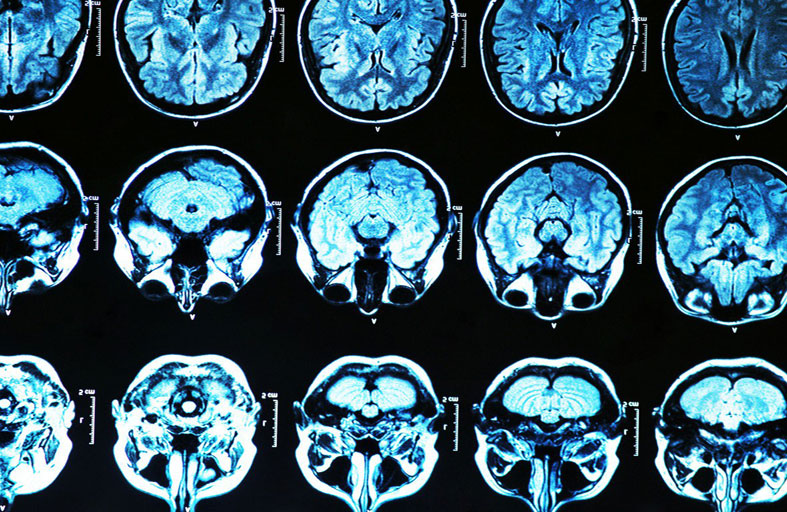

تمكّن باحثون من تطوير حاسوبي نجح في محاكاة تجربة إكلينيكية لتقييم فعالية علاجين لمرض الزهايمر، هما أدوكانوماب، ودونانيماب، وهما من أوائل الأدوية المصممة للعمل على ما قد يسبب مرض الزهايمر.

وأكدت النتائج ما بينته تجارب سريرية فعلية. حيث كان لكلا العقارين تأثير على إزالة لويحات بيتا أميلويد، وهي مادة موجودة في أدمغة الأشخاص المصابين بمرض الزهايمر.